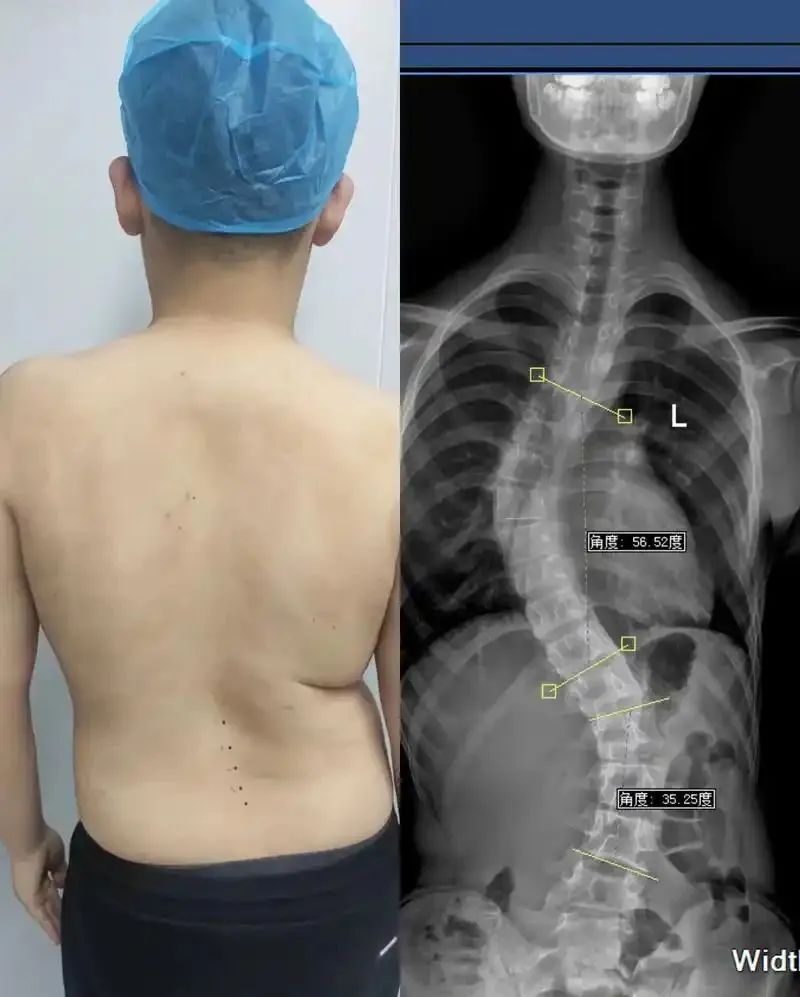

近些年,脊柱问题越来越严重,甚至越来越年轻化!

脊柱侧弯、脊柱炎、颈椎病、腰椎间盘突出...